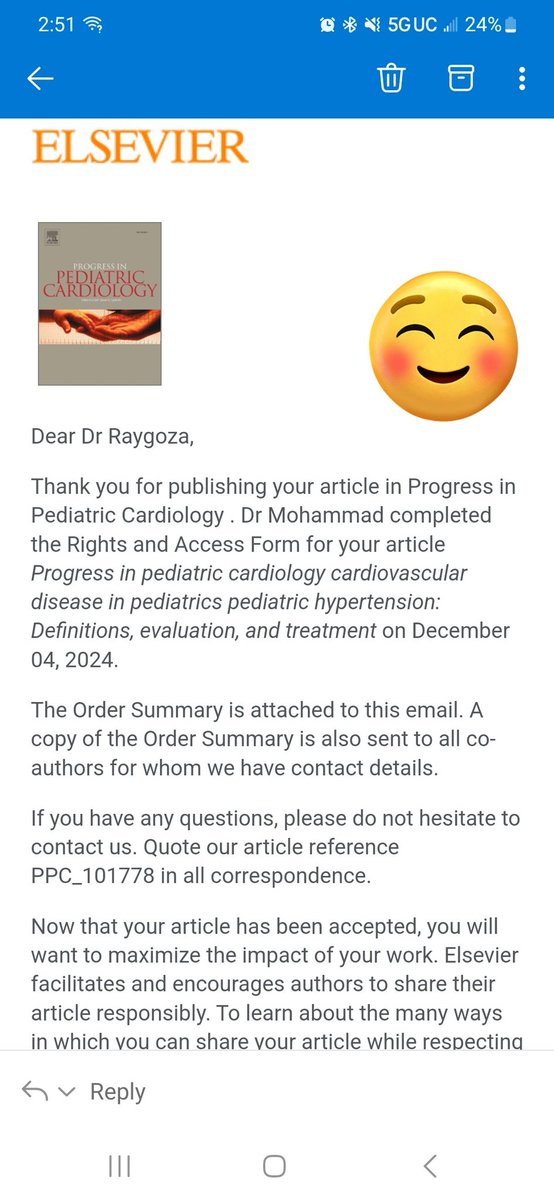

Co-author opportunity in Pediatrics Cardiology 🫀 forms.gle/iVkfqQfphA22kW… #Peds #Medical #researcher #student #publication